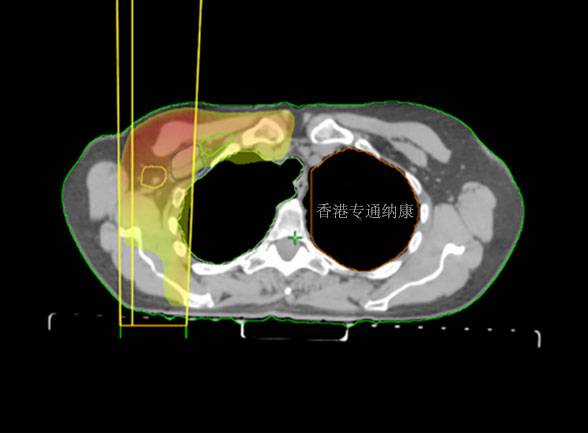

DS-8201是二代ADC药物,由抗HER2的IgG1单抗通过连接体,与拓扑异构酶Ⅰ抑制剂Dxd(效能比伊立替康高10倍)组成。

DS-8201通过选择性靶向HER2表达肿瘤、释放有效载荷拓扑异构酶抑制剂并导致细胞死亡,透膜性游离药物攻击临近癌细胞的作用(旁观者效应)。此外,DS-8201还能发回类似曲妥珠单抗的抗体依赖细胞街道的细胞毒性作用(ADCC)和Akt磷酸化抑制作用。